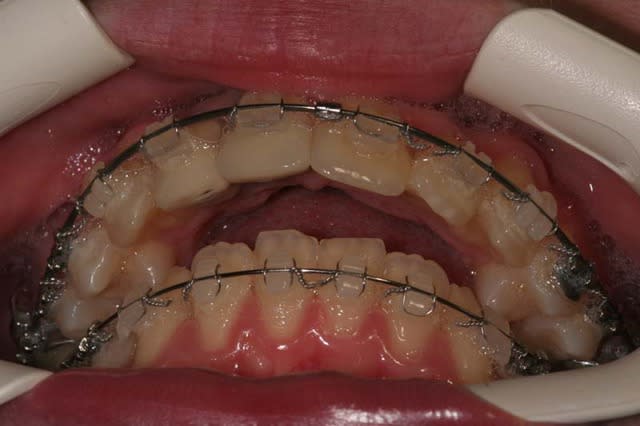

Voici le cas il y a 8 jours, c.a.d. 1 an et 1 mois après les photos de son dernier rendez vous

entre temps, elle est allée se faire faire des provisoires sur 12/11 par un confrère plus prés de son domicile

voici le résultat de l’absence de contention, qui aurait été (a mon avis) une erreur compte tenu que le cas n’était pas terminé

c’est mal foutu, c’est déglingué mais je n’ai aucune malposition Inc. Inf.

c.a.d. : AUCUNE RECIDIVE D’ENCOMBREMENT AVEC ROTATIONS

les dents ne sont pas alignées, mais j’ai mon espace globale, je peux poursuivre ce traitement avec sérénité

elle n’est pas défigurée,

elle n’a pas de migraines

pas d’acouphènes

pas de DAM.

etc ...

A votre avis pourquoi ?